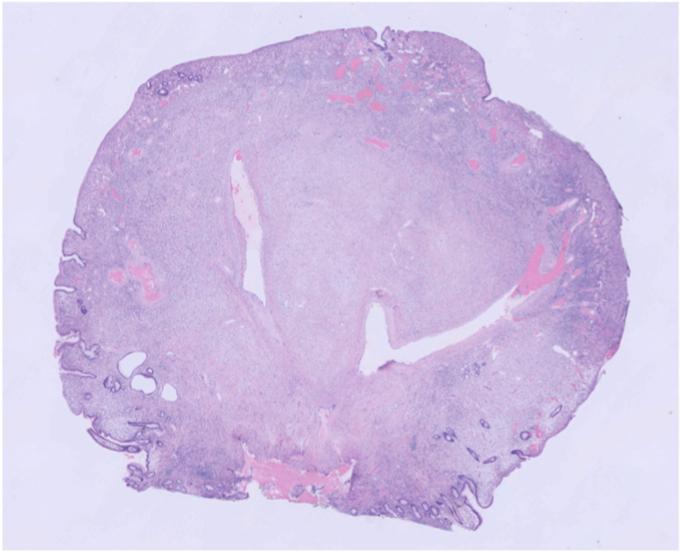

Video 1A case of an inflammatory fibroid polyp of the ileum that was safely resected using gel immersion EMR with double-balloon endoscopy.

视频1:一例回肠炎性纤维性息肉病例,通过双气囊内镜下凝胶浸泡内镜黏膜切除术安全切除。